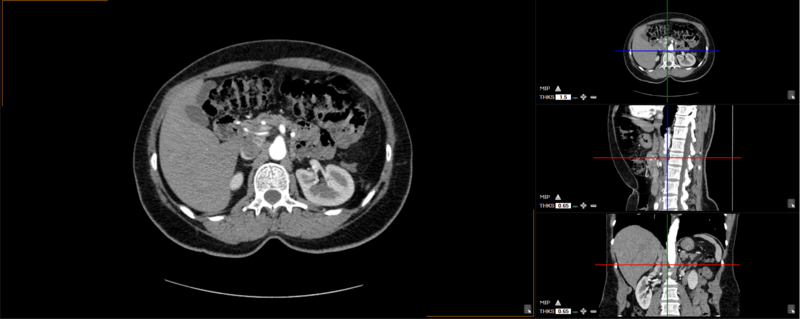

The user can choose from any of these predefined viewing protocols within the MPR mode:

Here are the different viewing protocols you can choose from: